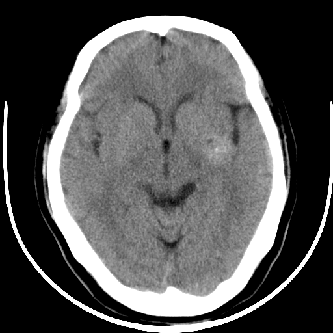

标题: CT4588:是出血吗?

44 f,平时头晕,有高血压病史,近日加重。其它检查无异常。

图象ct值是多少?品眼看密度像出血但周围没有水肿带也没有占位效应很难说

有肢体活动障碍吗?离左侧内囊后肢很近。不像是出血,如果是出血吸收期,周围应该有水肿

尽管密度类似于出血,但其密度明显不均匀,中间有多枚小点状致密影似钙化。同时,病灶周围没有水肿,没有占位效应,临床又没有其他症状。

首先考虑动静脉畸形,建议增强。

左侧豆状核后部不均匀高密度影,中间有斑点状钙化灶,周围无水肿及占位效应,考虑血管瘤。